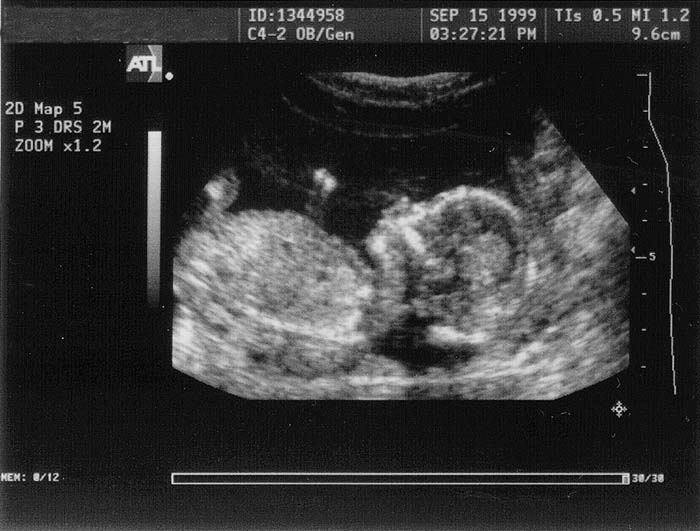

September 15, 1999

Click for larger picture.